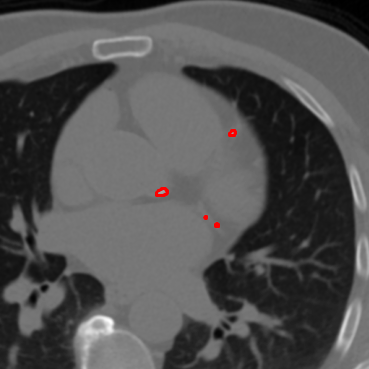

Refer to caption

(a) Annotated CT slice with annotation

(b) CT slice without annotation

(c)

(d)

(e)

(f)

(g)

(h)

Figure 2: Representation of guided local data augmentation. Figure a𝑎aitalic_a represents labeled CT slice, while b𝑏bitalic_b represents the same image without annotation. The figures from c𝑐citalic_c to hhitalic_h shows the guided local data augmentations utilized in DINO training.

Label-guided augmentation is effective for the data with only labels or prompt points. During the training phase, CT slices with annotations or labels are randomly augmented regardless of whether they have labels. In addition to this random augmentation, it is applied an augmentation which centers the center of annotated areas chosen randomly from labels. This point specific augmentation helps the model to emphasize on that labeled areas more than other randomly chosen and cropped areas. The point specific data augmentation or label-guided data augmentation has been applied for local data augmentations rather than global data augmentation, as the areas we want to highlight in features generated by DINO contain more localized information. The Fig. 2 represents locally guided data augmentation on a CT slice which includes a calcification. In our experiments, random local data augmentation was set to 8888, while guided local data augmentation was set to 6666, in order to preserve the randomness of the local data augmentation process. To illustrate the contributions of guided data augmentation, Fig. 3 presents a visualization of the outputs from the self-attention heads of DINO models trained using both label-guided and standard methods.